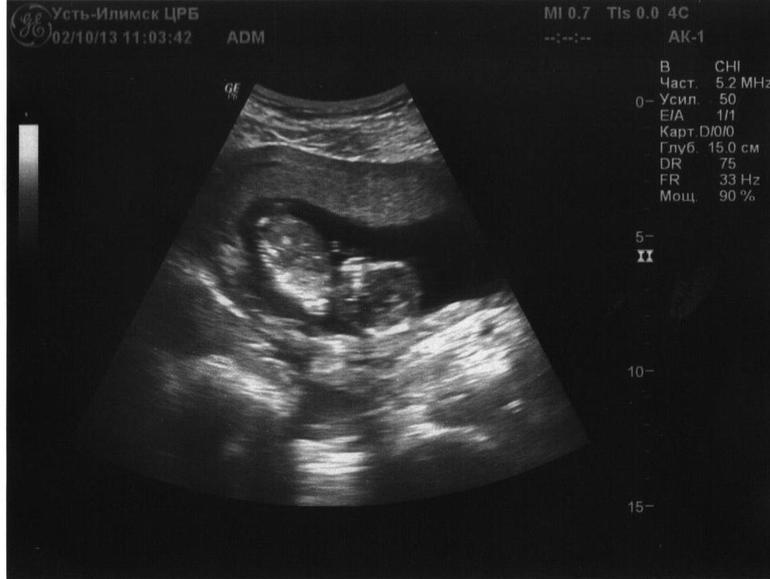

Кое-как дождавшись вечера – платный прием УЗИ у нас по вечерам – мы поехали с мужем в больницу. Слава Богу все хорошо!

И как бонус ко всему пережитому за тот день – мы узнали пол. У нас будет Доченька!

90% вероятности. У меня пока что еще 18-19 недель. А плановое узи должно быть на 20-21. Буду ждать еще)

Мы видели нашу маленькую крошку)) особенно рада, что муж увидел – он вахтами работает – на плановое узи может и не попасть.

Мы видели как она шевелила ручками. Большая стала уже. Месяц назад совсем еще крошечка была) Чудо просто какое-то!

УЗИ

2.10.13